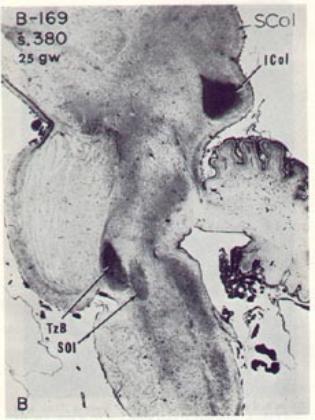

Figure 9 – Myelin at 25 gestational weeks

Figure 9: Myelin in the human brainstem

auditory pathway at 25 gestational weeks,

sagittal view.

SCol=superior colliculus,

ICol=inferior colliculus,

TzB=trapezoid body,

Sol=superior olive.

(from Yakovlev and Lecours, 1967).